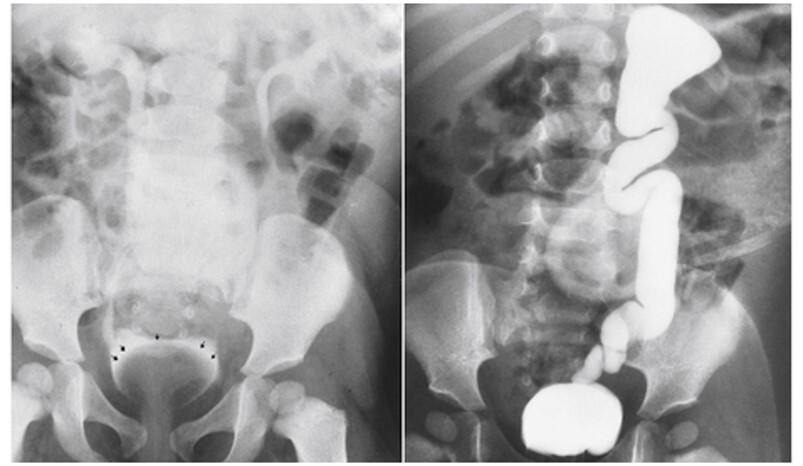

1

Q

What pathology is seen here?

A

Unilateral Renal Agenesis

2